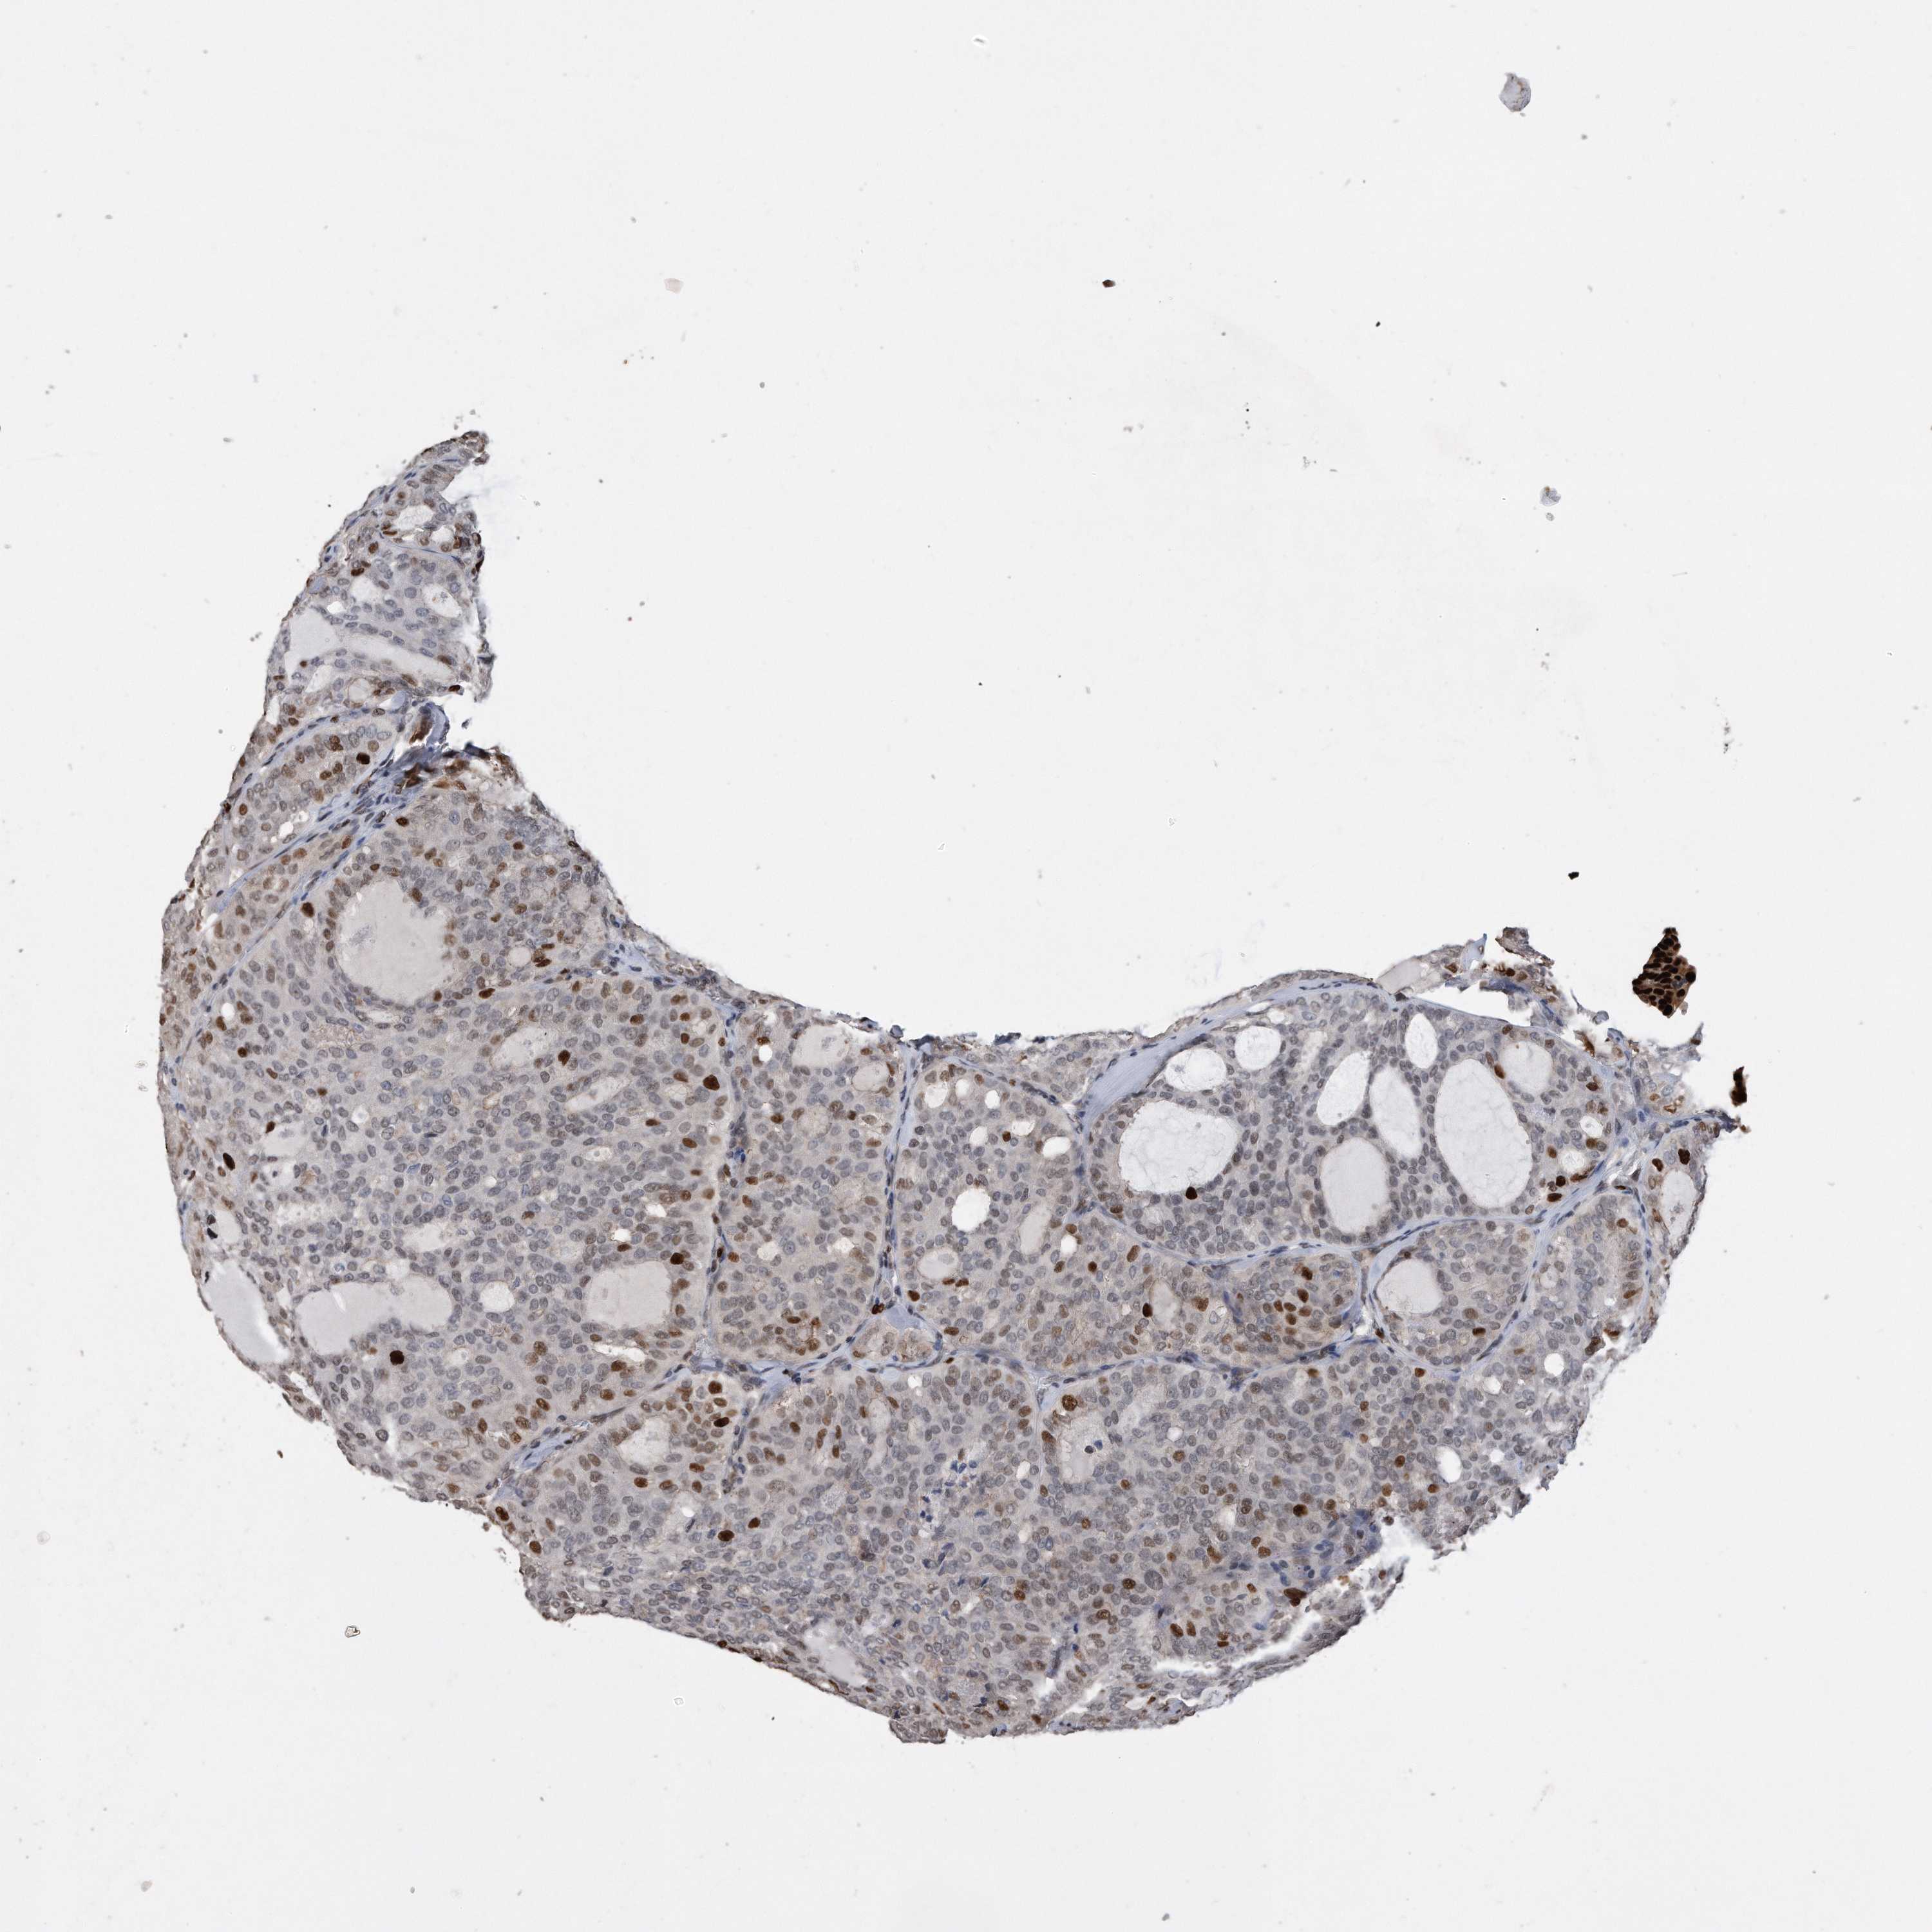

THYROID CANCER - Protein expressioni

A mouse-over function shows sample information and annotation data. Click on an image to view it in a full screen mode. Samples can be filtered based on level of antibody staining by selecting one or several of the following categories: high, medium, low and not detected. The assay and annotation is described here.

Note that samples used for immunohistochemistry by the Human Protein Atlas do not correspond to samples in the TCGA dataset.

Antibody stainingi

Antibody staining in the annotated cell types in the current human tissue is reported as not detected, low, medium, or high, based on conventional immunohistochemistry profiling in selected tissues. This score is based on the combination of the staining intensity and fraction of stained cells.

Each image is clickable and will lead to virtual microscopy that enables deeper exploration of all samples and also displays staining intensity scores, fraction scores and subcellular localization as well as patient and tissue information for each sample.

Papillary adenocarcinoma, NOS

Follicular adenoma carcinoma, NOS

Carcinoma, NOS